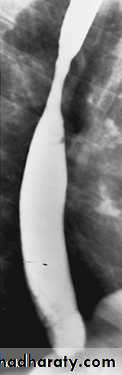

Stricture

Benign vs. malignant Causes Specific locationContrast study EUS CT